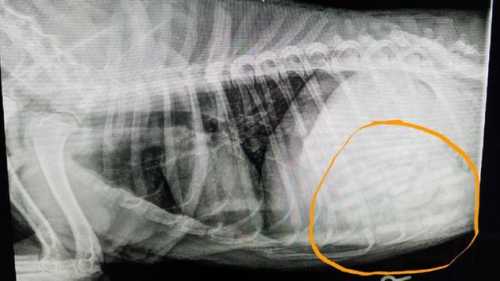

The case of the missing pacifiers was solved when the baby's grandmother saw the family dog, Dovey, swipe one off the counter. The Oklahoma family took Dovey to the veterinarian's office and x-rays showed the missing pacifiers. Dovey had slowerd her eating and was vomiting for a few days. Initially the vet thought there were seven to nine pacifiers in Dovey's stomach, but...[ Read More... ]